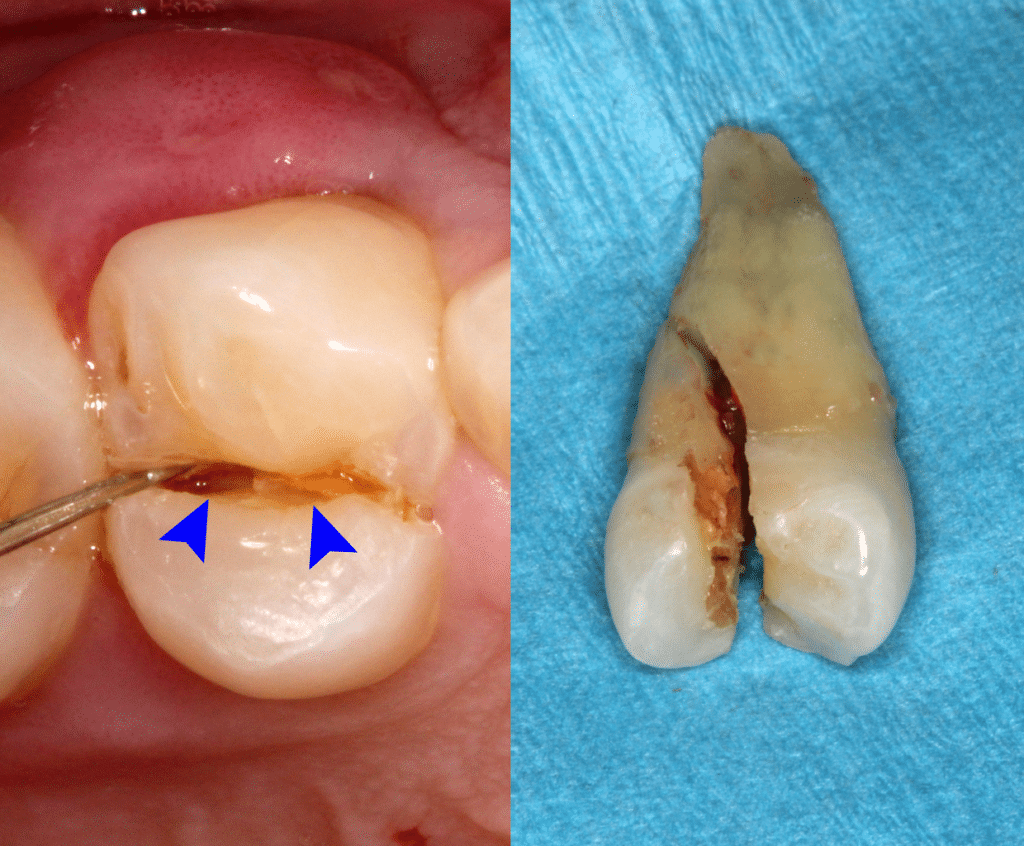

하지만, 치아의 균열 정도가 심한 경우에는 예후가 그리 좋지만은 않습니다. 균열이 치아 뿌리 근처까지 진행된 경우에는 이러한 틈을 통해 자극원들이 계속적으로 치아 내부로 들어와 예후가 불량합니다. 치아가 완전히 분리된 경우(split tooth)는 발치 외에는 다른 방법이 없습니다. 발치 후 생긴 공간에는 임플란트나 브릿지 치료로 저작 기능을 회복시켜 줄 수 있습니다. 이렇듯 겉보기에는 치아에 큰 이상이 없어 보이더라도 균열의 진행 정도에 따라 최종적으로 치아를 잃게 될 수도 있습니다.